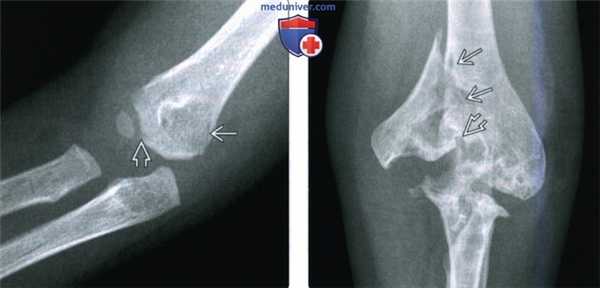

(Слева) На передне-задней рентгенограмме локтевого сустава у ребенка младшего возраста визуализируется характерная в этом возрасте тонкая линия перелома латерального мыщелка. Здесь невозможно увидеть повреждение эпифизарного хряща и суставной поверхности, но это следует предположить.

(Справа) Передне-задняя интраоперационная ренттеноартрограмма у этого же пациента подтверждает анатомическое сопоставление поверхностей суставного хряща после репозиции.

(Слева) На передне-задней рентгенограмме перелома латерального мыщелка у двухлетнего ребенка виден отделившейся костный отломок. Слабо выраженный перелом через ростковую пластинку подтверждает, что это повреждение Салтера-Харриса.

(Справа) На боковой рентгенограмме у этого же пациента определяется перелом латерального мыщелка с незначительным отделением метафизарного участка. Ростковая пластинка повреждена.